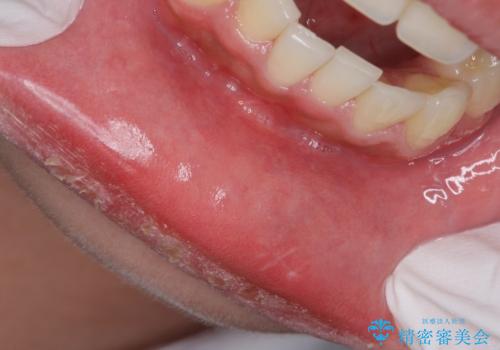

実はこんなに磨き残しが!!!

担当医 歯科衛生士